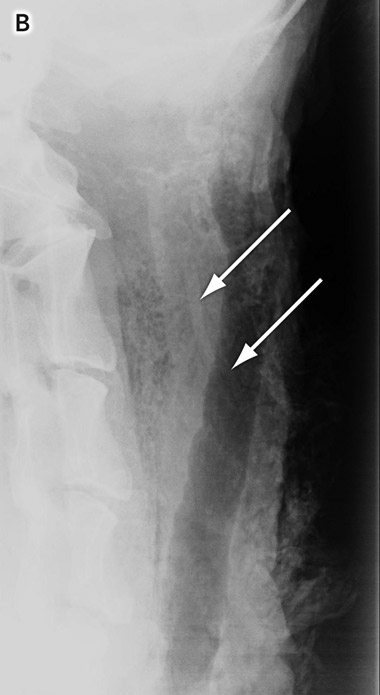

The specimen was prepared by removing excess wool and dissecting the laryngopharynx. The fishbones were placed in the paratracheal tissues and adjacent to the larynx (Box 2, A).